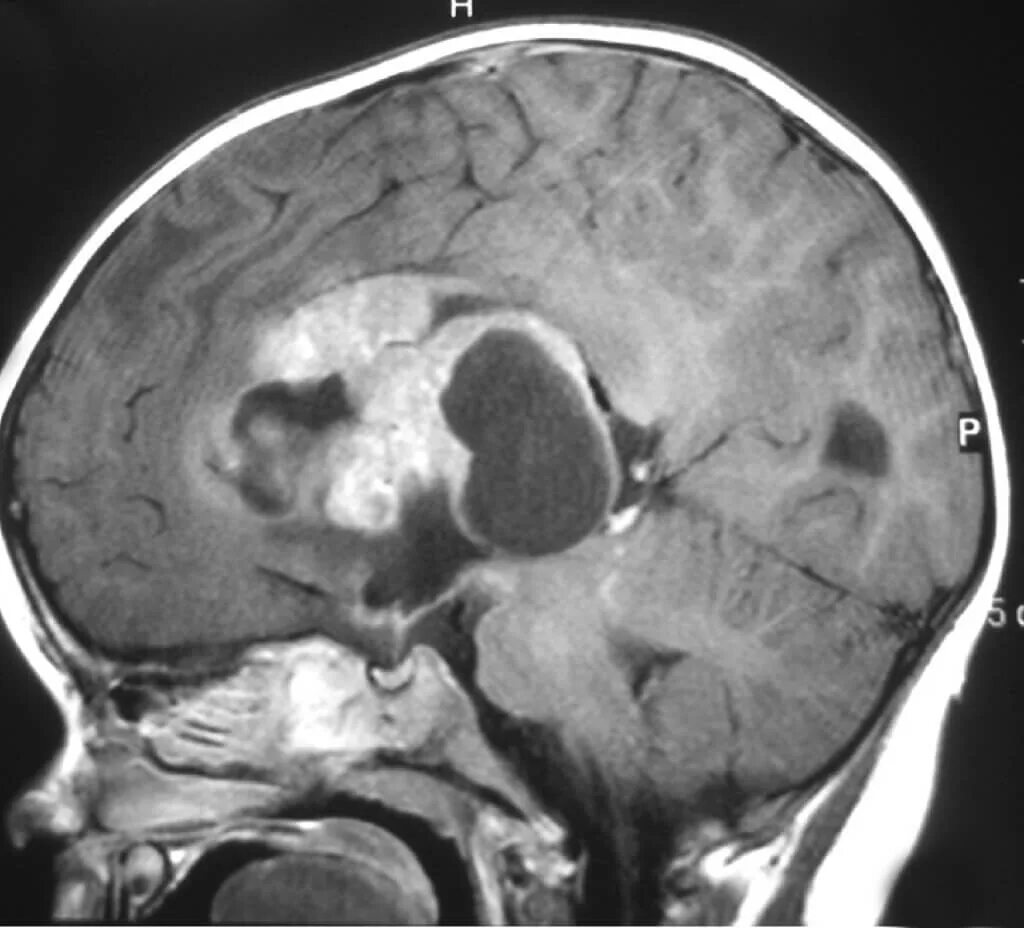

От чего может быть опухоль